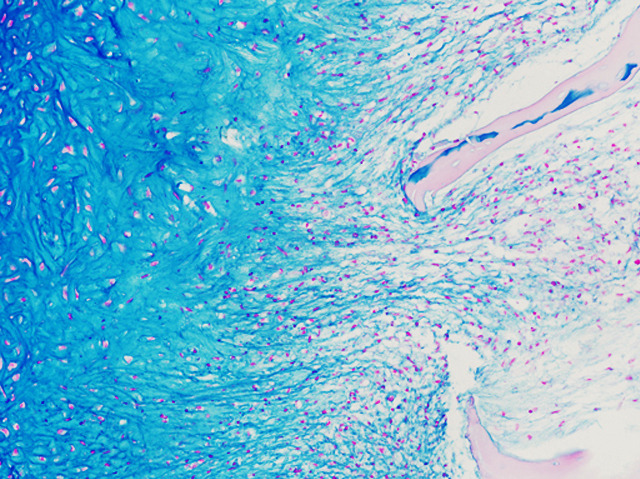

Creating Cartilage

Human fat is one of the most practical sources of stem cells. But coaxing these precursors to become cartilage – the flexible connective tissue between our joints and elsewhere – has so far proven difficult. Now researchers have managed to do it by mimicking a process that occurs naturally in the body. By exposing stem cells in a dish to a protein called factor-β, the scientists induced them to undergo condensation, a DNA-compacting process that defines growth and differentiation of cells, as they do in the body before starting to make cartilage. Pictured is a section of the lab-grown tissue with its swirling blue-stained proteoglycan – a key component of cartilage – and bone substrate (the long pale pink projections). The ability to create functioning cartilage could have tremendous clinical advantages, accelerating the development of new treatments for cartilage repair.